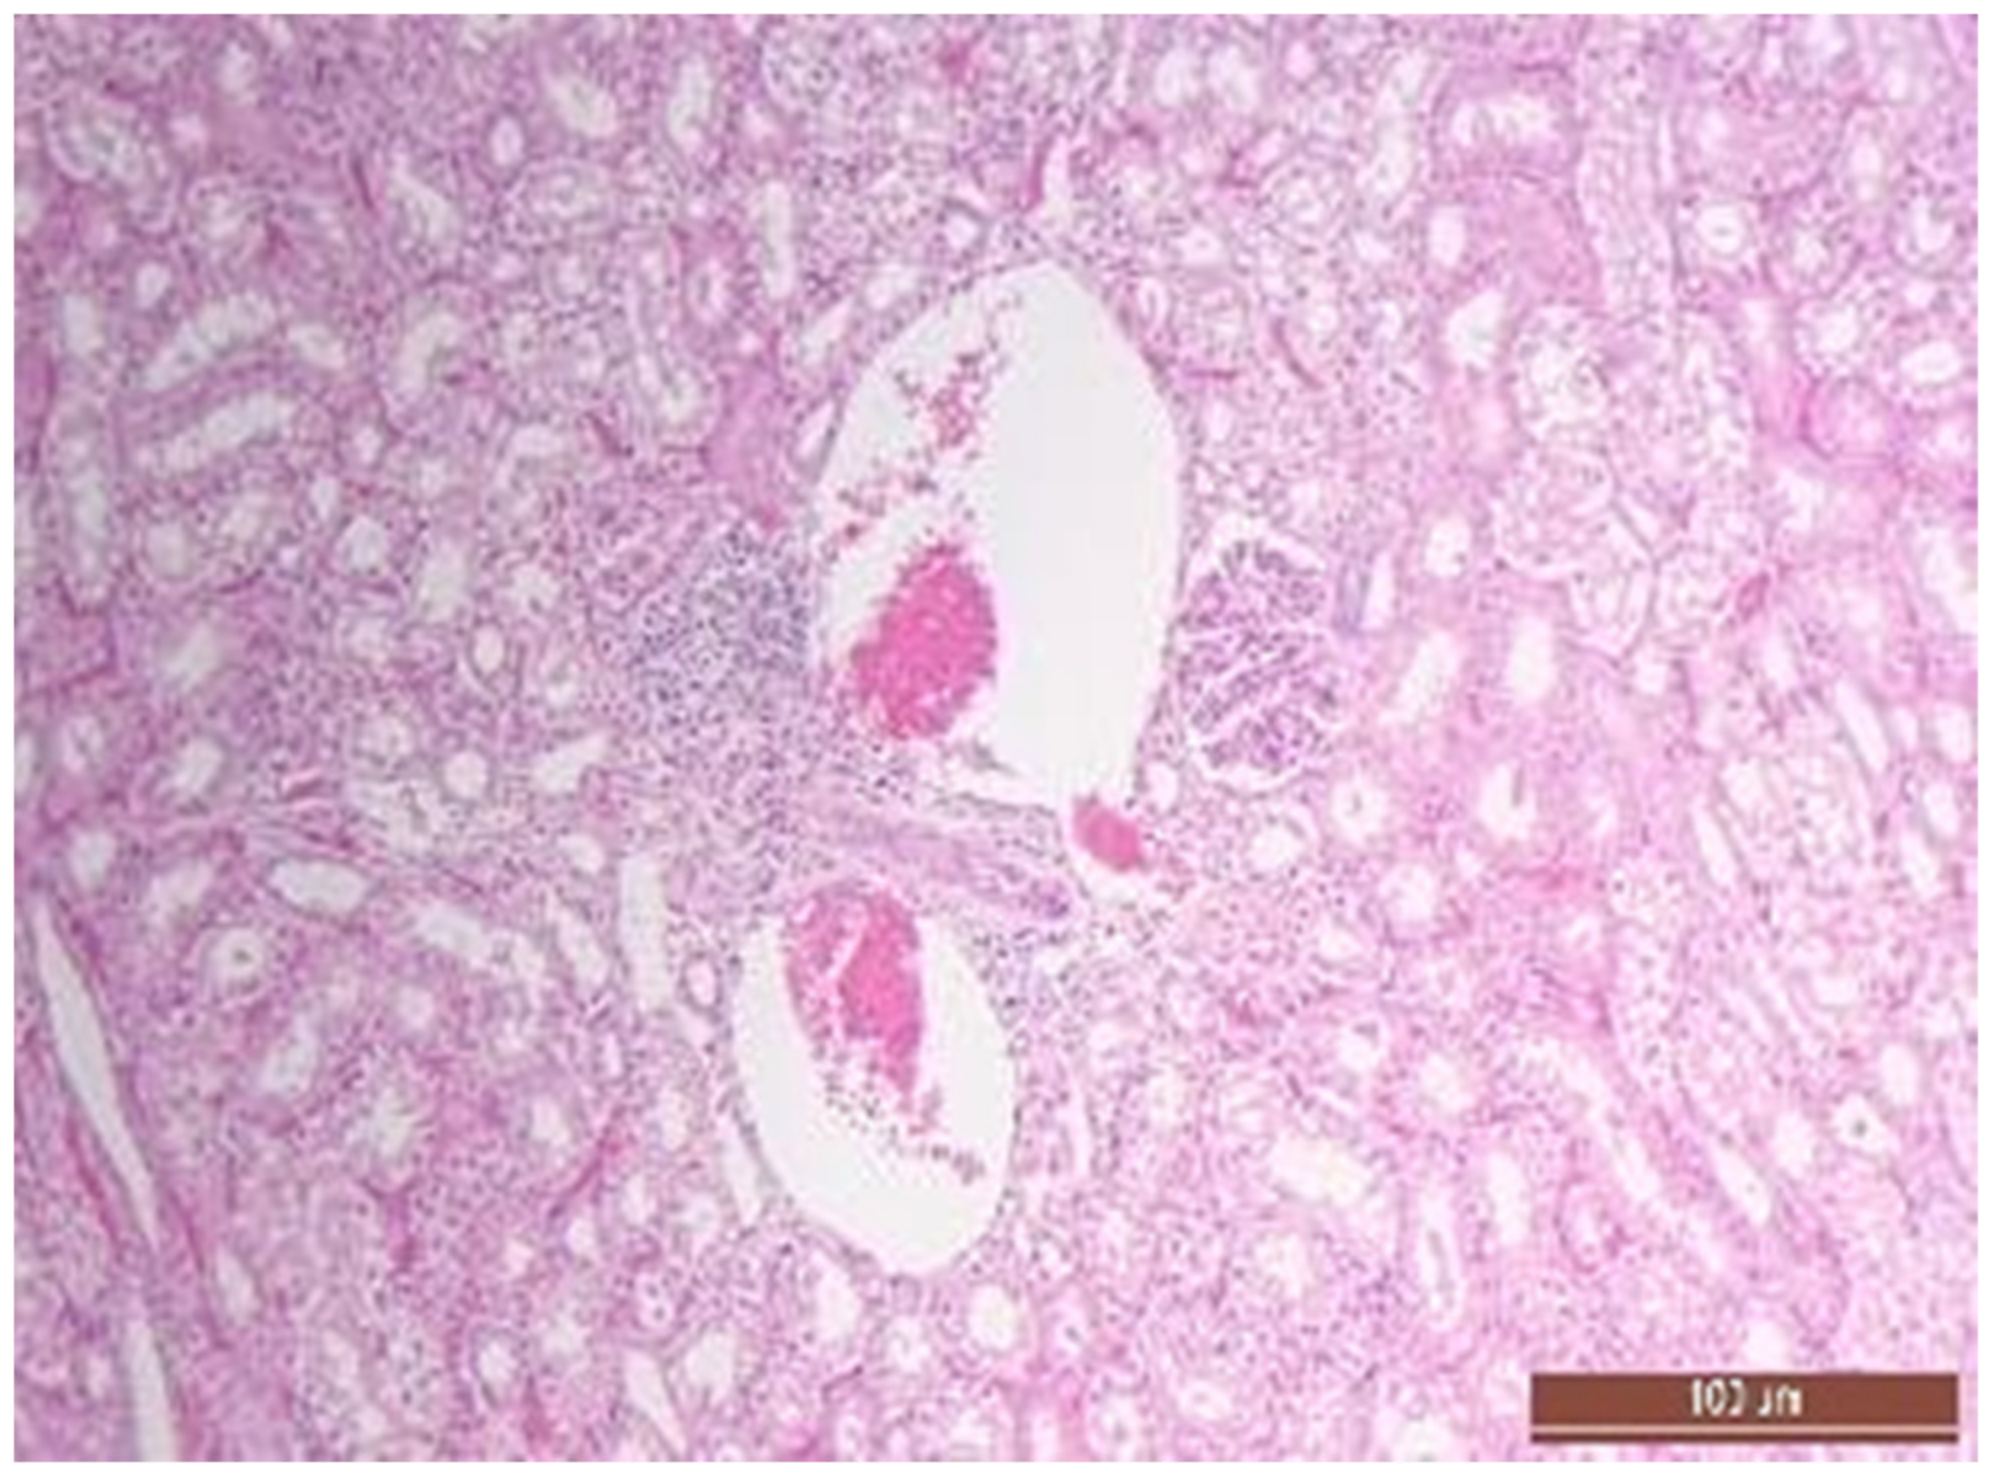

2.5. Pathomorphology

3.4. Pathology of Kidneys